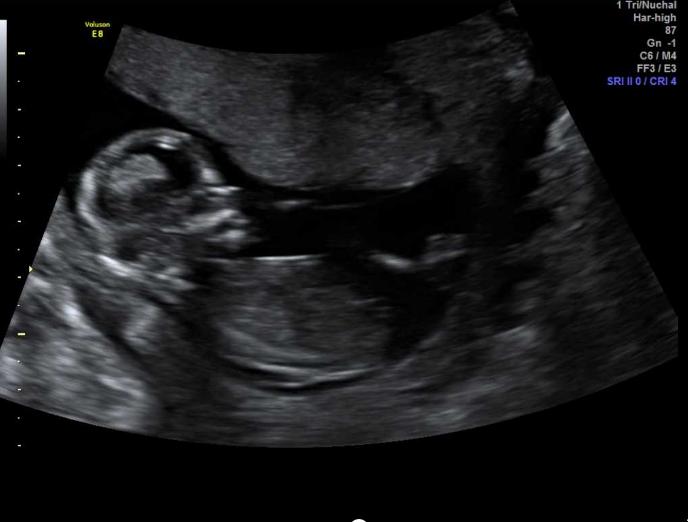

Girl lean based on second pic from the botttom but none of the pics really show the nub clear enough for me to be super confident.

I am guessing girl based on the 5th pic.

Congratulations on your pregnancy Pink! Girl guess from me especially the second last pic! Have you posted your second sway?